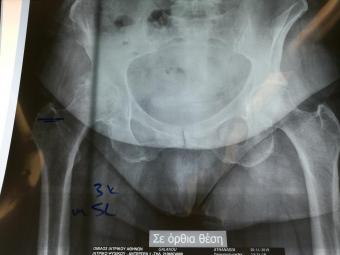

Компанія Lima надала стажування в ортопедичній приватній клініці місті Афіни Греція в листопаді 2019 року. Ендопротезування кульшового суглоба протезами компанії Lima малоінвазивним передньо-латеральний доступом у професора Христодулоса.